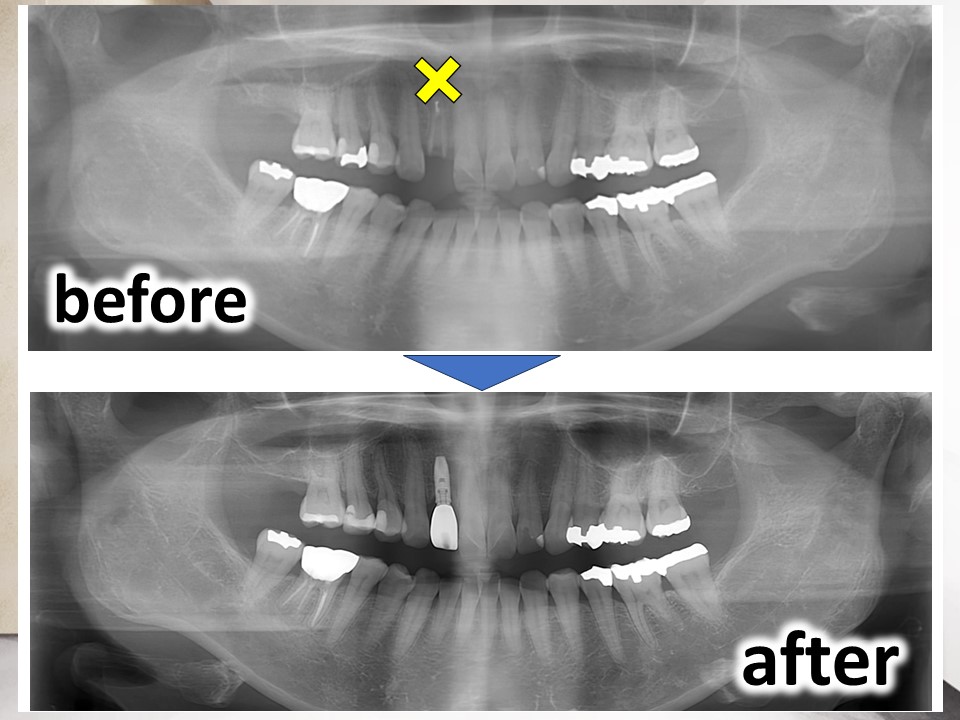

今回は、右上の前から2番目の歯の欠損に対して、インプラント治療を行った症例について供覧いたします。

診断:右上2 C4(抜歯が必要な重度の虫歯)、インプラントを埋入するには残存骨が不足している

治療:右上2の抜歯、人工骨を用いた骨造成(GBR)、インプラント治療

他院にて、右上2は抜歯といわれたものの、同部のインプラント治療は難しいといわれ、何とかインプラント治療ができないかということで当院を受診されました。

インプラント治療により、見栄えだけでなく、しっかり咬めると機能も改善でき、患者さまには大変満足いただいております。